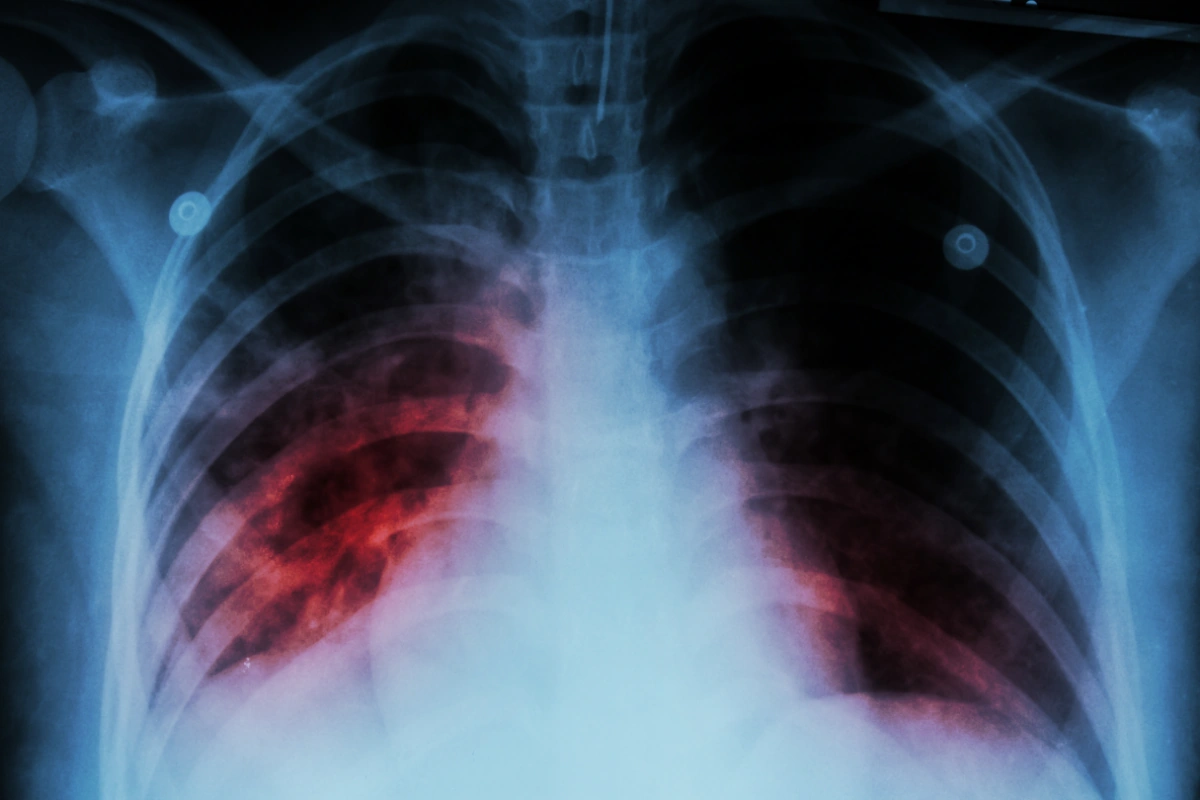

Ötən il 198 uşaq və yeniyetmə vərəmə yoluxub

Ötən il 198 uşaq və yeniyetmə vərəm xəstəliyinə yoluxub.

APA xəbər verir ki, bunu Səhiyyə Nazirliyi Elmi Tədqiqat Ağciyər Xəstəlikləri İnstitutunun direktoru İradə Axundova deyib.

O bildirib ki, 2024-cü il üçün bu göstərici 278 olub.

"2015-ci ildə hər 100 min nəfərə düşən vərəmlə xəstələnmə göstəricisi 41,1 olduğu halda, 2025-ci ildə bu rəqəm 21,5-ə enib. Vərəm xəstələrinin təxminən üçdə ikisini kişilər, üçdə birini isə qadınlar təşkil edir. Xəstəliyin aşkarlanma səviyyəsi də əhəmiyyətli dərəcədə artıb. Belə ki, 2015-ci ildə bu göstərici 53 faiz olduğu halda, 2025-ci ildə 86 faizə çatıb”, deyə o bildirib.